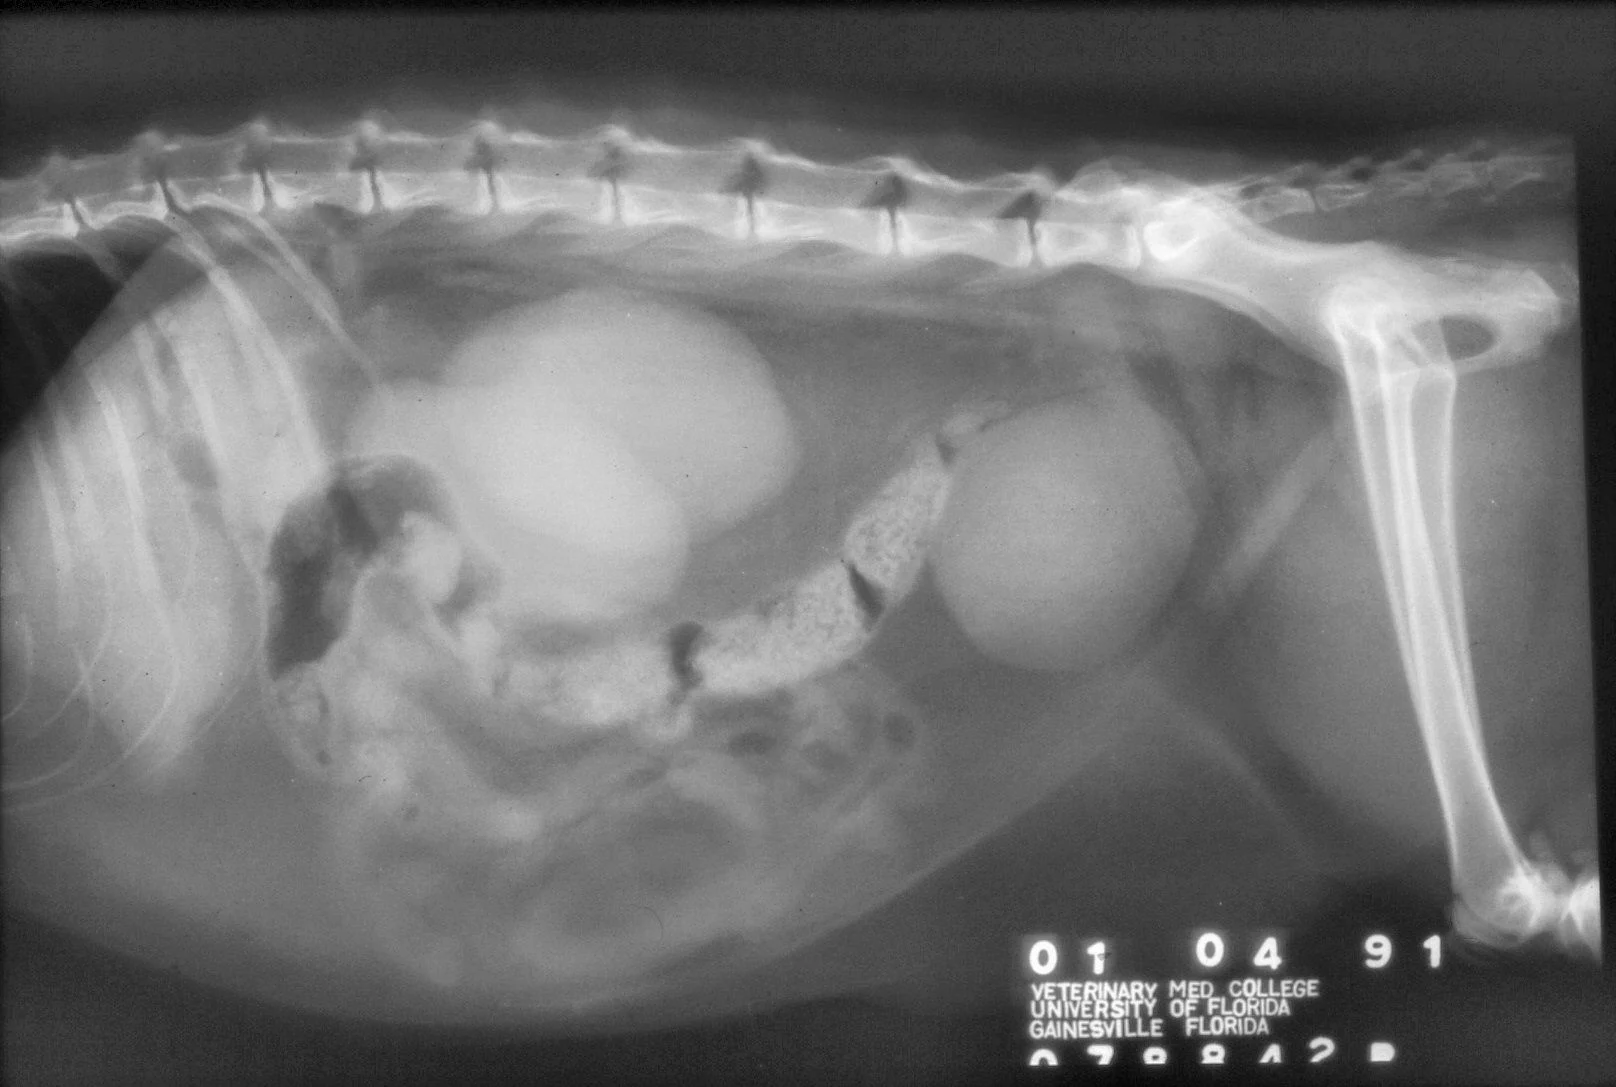

Abdominal radiographs will show only an enlarged kidney or kidneys (Figure 2A), but excretory urography will show renal pelvis dilatation (Figure 2B). Ultrasonography will also show hydronephrosis, renal parenchymal disarray, and necrotic debris in the renal collecting system (Figure 3).

Abdominal radiographs of a cat with bilateral pyonephrosis; a cystotomy performed 6 months previously had caused bilateral ureteral obstruction at the urethral junction (A and B). Pyelography was done by pyelocentesis, and bilateral hydronephrosis is shown.